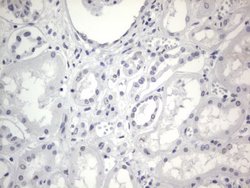

| Immunohistochemistry (Paraffin), Western Blot | |